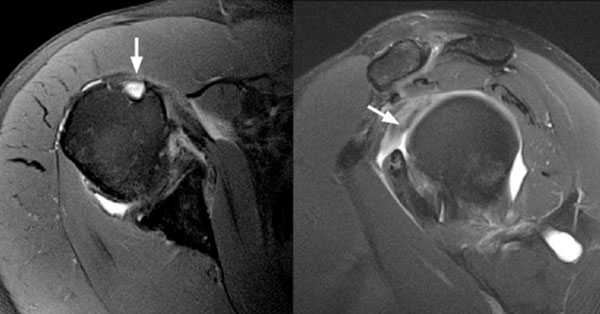

Для уточнения диагноза, определения степени повреждения подключают дополнительные методы обследования. Широко используется УЗИ, метод позволяет безошибочно определить полные разрывы. Для получения более точной информации о локализации повреждения, а также для визуализации небольших надрывов и внутрисуставных повреждений применяют МРТ.

Рис.3 МРТ-картина разрыва сухожилия длинной головки бицепса